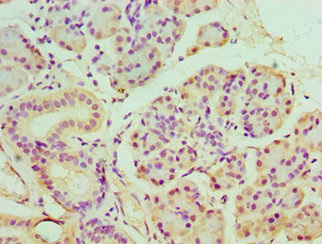

Immunohistochemistry of paraffin-embedded human breast cancer using CSB-PA854079ESR1HU at dilution of 1:100